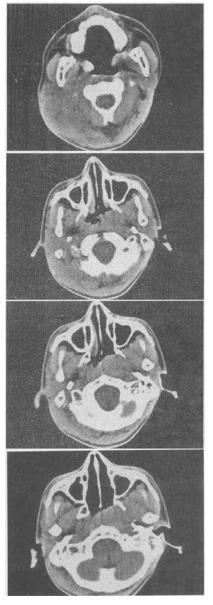

男,17岁,自诉鼻涕中带血3个月,伴耳鸣、听力减退,无发热,影像检查如图,最可能的诊断是()。

A、咽旁脓肿

B、鼻咽部恶性淋巴瘤

C、鼻咽癌

D、小唾液腺混合瘤

E、鼻咽部淋巴组织增生

C